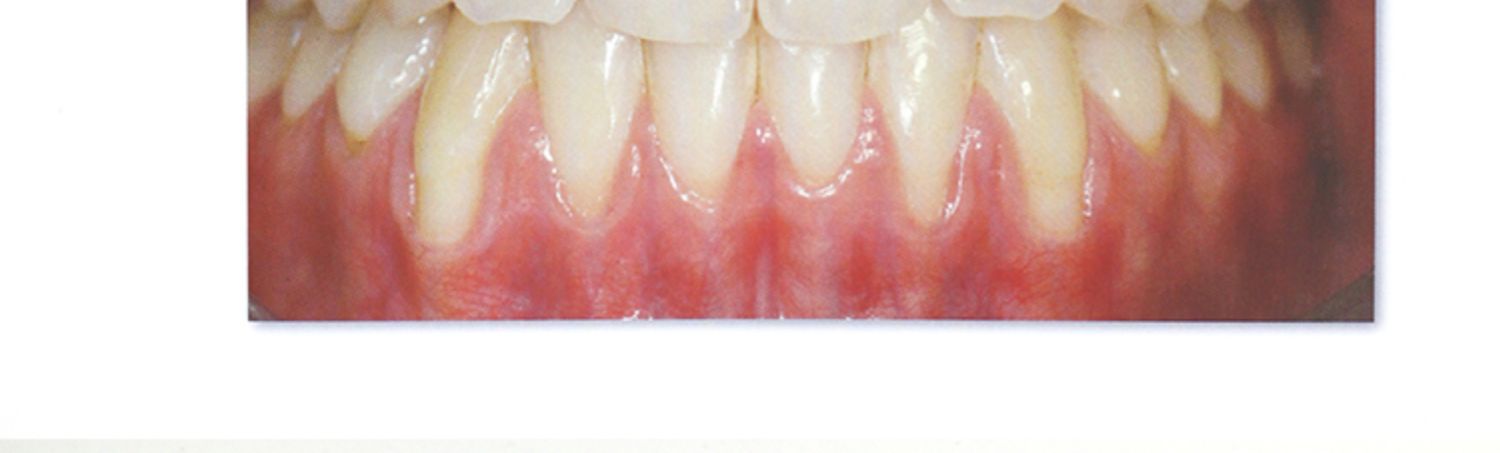

膜齦美學手術用於治療膜齦美學的异常改變。 這些异常改變可能是由牙齦退縮導致的,且常常伴發非齲性頸部病變/或根面齲,另外與之相反的情况是,被動萌出异常也會導致膜齦美學的异常改變。 膜齦美學手術的目的還包括新增修復體或種植體周圍的牙齦厚度和高度,以及無牙區牙槽脊上的軟組織增量。 無牙區牙槽脊增量手術科技將在第二卷書中探討。 本卷中所描述及闡明的膜齦手術科技是應用於天然牙和種植體,且其主要目的是滿足患者的美學需求。